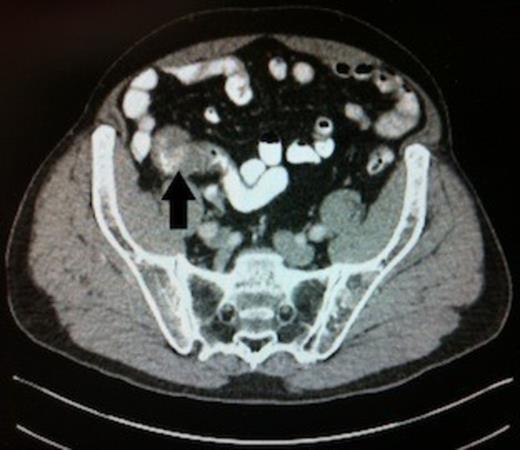

Abdominal CT scan, black arrow highlighting the carcinoid tumour in the distal ileum

CT scanning demonstrated the lesion intususscepting into the terminal ileum. There was no evidence of lymphadenopathy and no metastatic deposits were visualised. (Figure 2)